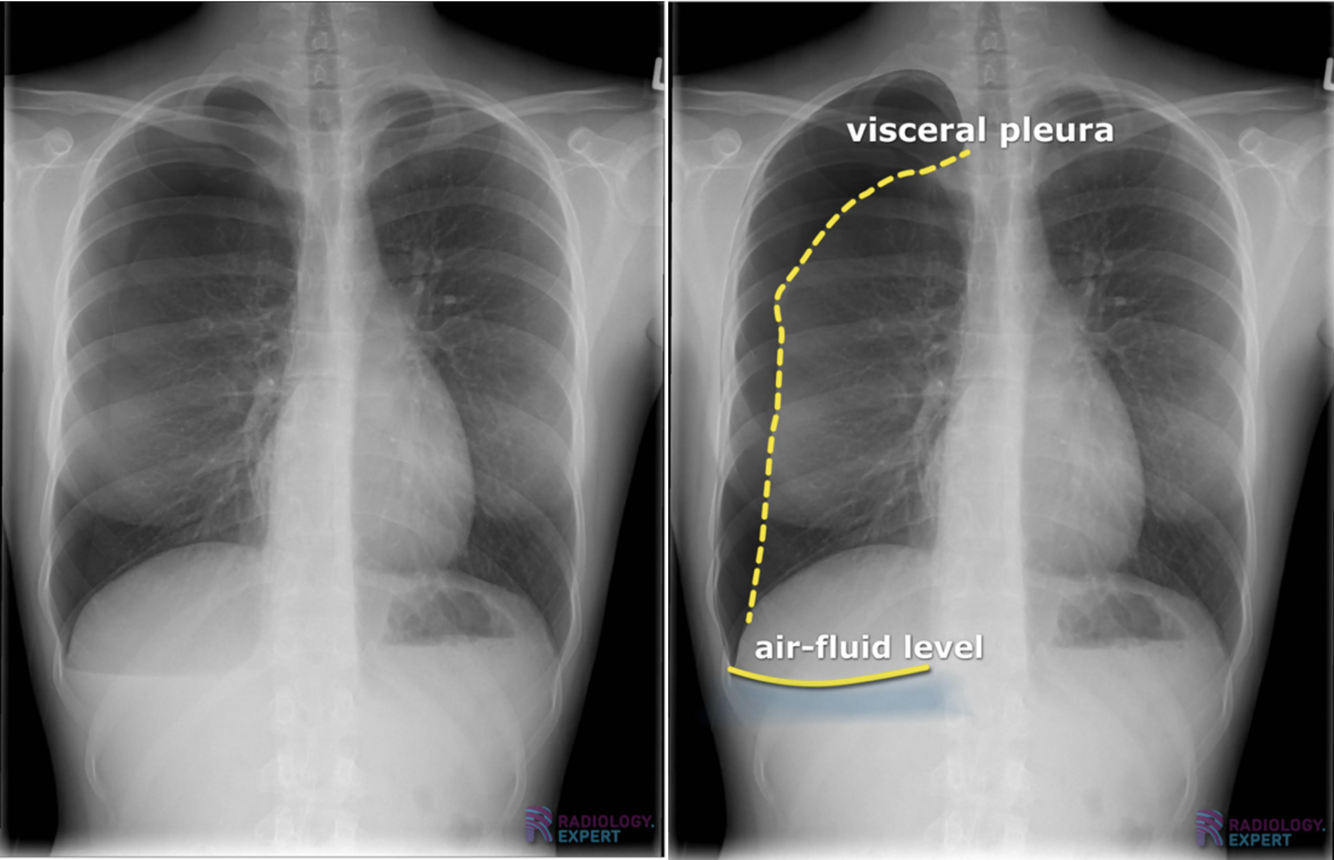

Pleuraeffusion (pleuravæske):

Kan bestå af:

* Serøs væske – Hydrothorax

* Blod – Hæmothorax

* Lymfe – Chylothorax

* Pus – Empyem